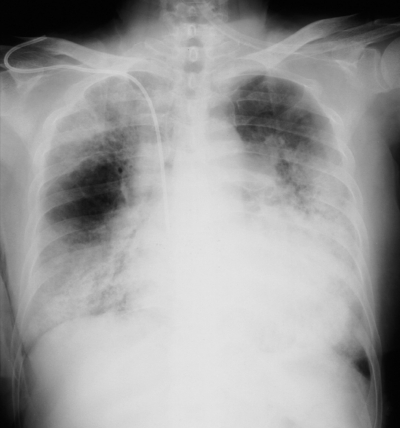

血液所見:Hb 6.2 g/dL。CRP 3.6 mg/dL。胸部エックス線写真と肺野条件の胸部CTとを別に示す。喀痰の塗抹、培養検査は一般細菌、抗酸菌ともに陰性で、結核菌の PCR 検査も陰性である。気管支肺胞洗浄液は鮮紅色で、ヘモジデリン貪食マクロファージを認める。